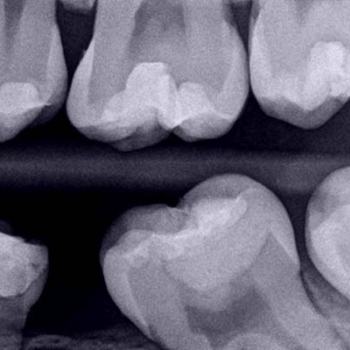

Pacienta s-a prezentat raportând durere de scurtă durată la dintele nr. 19 (Fig. 1). Prin radiografie, o evaluare clinică și o analiză a istoricului clinic al pacientei a fost diagnosticată o leziune carioasă extinsă (Fig. 2) ca și cauză a durerii, ca urmare a unui proces de pulpită reversibilă.

Fig. 2. Radiografia mușcăturii evidențiază o leziune carioasă a dintelui 19. Țesutul submineralizat este găsit în apropierea cornului pulpar mezial.